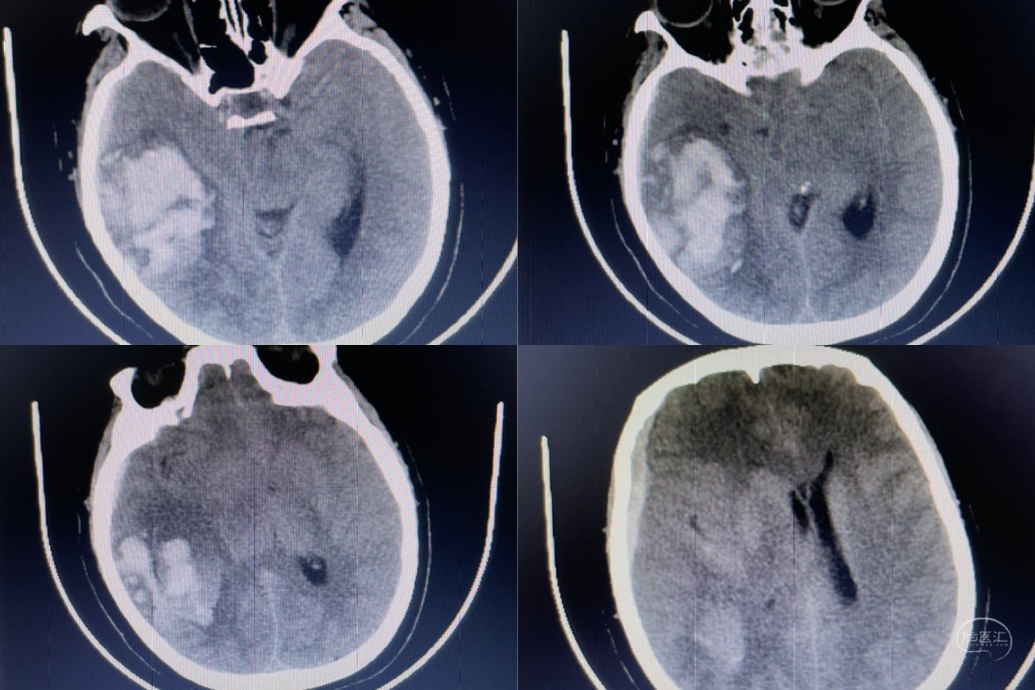

入院ct提示:右侧颞叶大量脑出血

颞叶血肿破溃形成硬脑膜下血肿

进一步增加脑出血颅内占位效应 颅内高压

患者入院时昏迷状态,脑疝